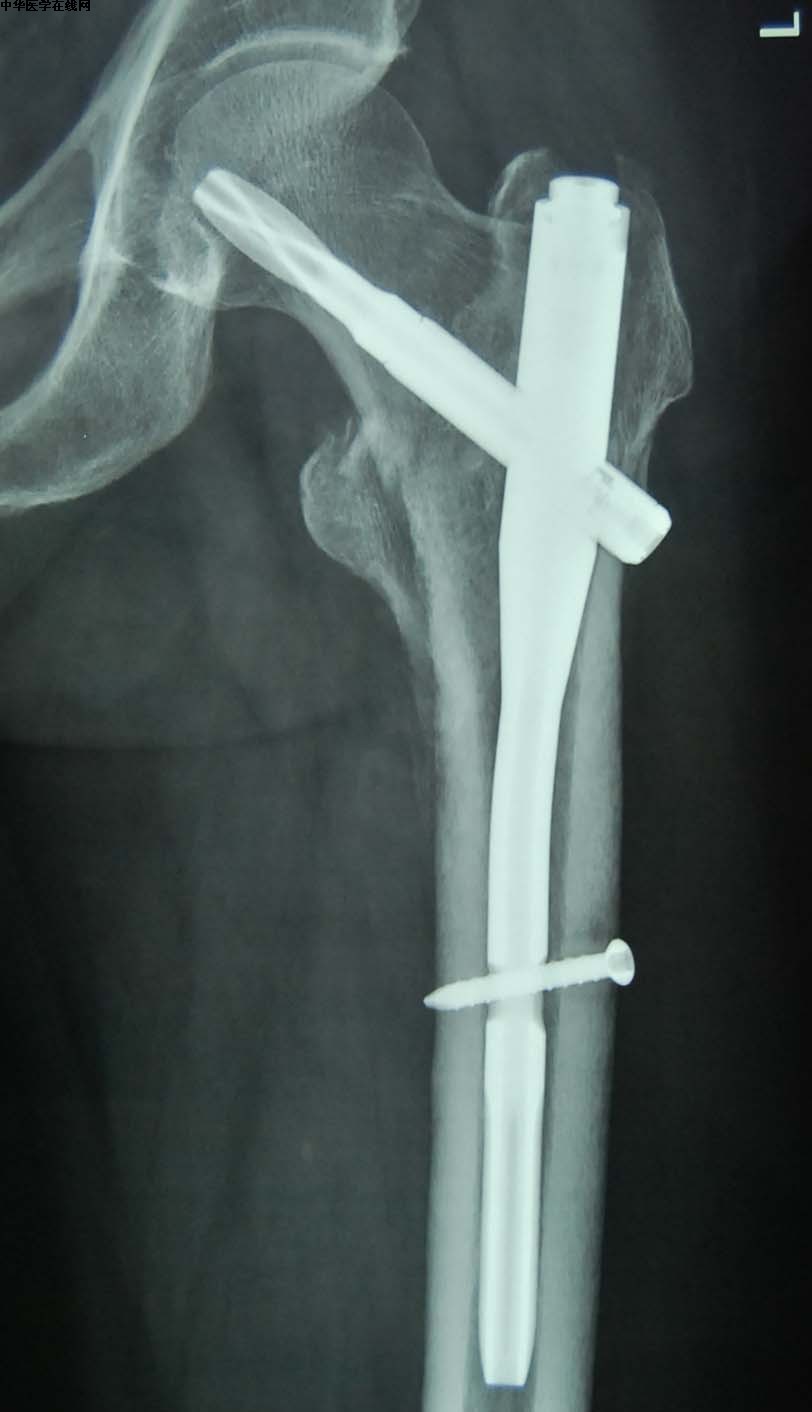

粗隆间骨折——

C:髓内钉固定

就是在骨髓内打入固定用的钉棒。由于这个部位的骨折往往都是高龄患者,带有严重的骨质疏松,一摔往往都是粉碎性的,破镜很难重圆,因此通过这种插入髓腔的髓内钉技术,就像穿糖葫芦一样,给断掉的骨头一个主心骨。让骨头自己愈合。

同时呢这个手术是一种微创技术,只需要开2-3个很小的切口就可以完成。做的熟练的骨科医生,从切口到完成手术只需要20分钟。

由于这种也是需要等到骨折愈合一定程度了才能下地复杂,因此也面临一段时间的卧床问题。有的患者可能会问,那为什么同样是高龄的人,这种骨折不能用人工关节呢,其实对于一小部分粗隆间骨折也是可以做人工关节置换的,但是手术要求啊,效果啊,难度啊,比股骨颈骨折要差一些和复杂一些,因此现在主流的技术还是髓内钉技术。

D:动力螺钉技术(钢板+钉)

这种技术是以前的经典技术,目前在一些没有普遍开展髓内钉技术的地区和医院,仍然是治疗粗隆间骨折的主要技术。

但是有一些碎的特别厉害的粗隆间骨折或者位置比较特殊的骨折,没法用髓内钉的,有时候还必须得用这种相对传统的手术方案。